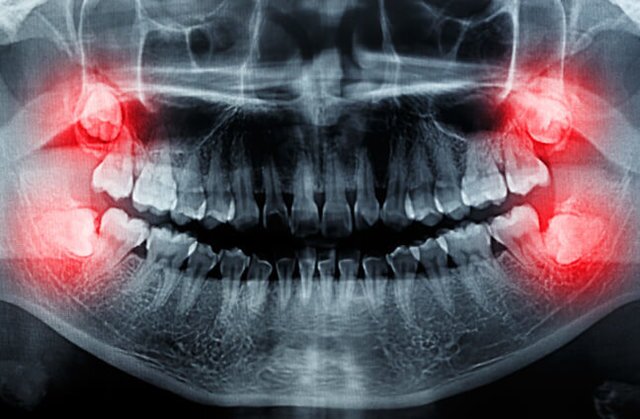

دندانهای عقل یا سومین و آخرین مجموعه دندانهای آسیاب پشتی جزو آخرین دندانهایی هستند که در دهان رشد میکنند. «ارسطو»، فیلسوف و متکلم یونانی در قرن چهارم قبل از میلاد، نوشته است که این دندانها حولوحوش ۲۰ سالگی درمیآیند. البته به مواردی از رویش دندان عقل در افراد بالای ۸۰ سال هم اشاره کرده است.

دندانهای عقل در انسان برای بهتر خرد کردن غذاهای سفت مانند گیاهان خام، گوشت و مغزها تکامل پیدا کردند اما با نرمتر شدن رژیم غذایی و بزرگتر شدن مغز در گونه انسانی ما، جمجمهها بزرگتر و آروارهها کوچکتر شدند؛ آنچه باعث شد دندانهای عقل چون مهمانی ناخوانده در دهان باقی بمانند که هم فضایی گرانبها را اشغال کردهاند و هم درد و ناراحتی ایجاد کنند و هنوز نفهمیدهاند که دیگر قدمشان روی چشم نیست! آنها با ایجاد تراکم بیش از حد دندانها در فک دردی مزمن به وجود میآورند و اگر هم نهفته و پنهان در لثه بمانند (بر اثر فشار به لثه یا دندانهای دیگر) ممکن است مشکلات سلامتی مانند پوسیدگی و عفونت ایجاد کنند. از طرفی افراد گرفتار با عوارض دندان عقل اغلب برای جویدن مشکلاتی دارند و دهانشان بوی بدی میدهد.

نتیجه اینکه کشیدن دندان عقل (ادنتکتومی) بسیار رایج است و مردم در سراسر جهان چندین دهه است که انتخابشان این است که از طریق جراحی دندان عقل را از دهانشان خارج کنند، زیرا این دندانها قابلیت خاصی ندارند و میتوانند مشکلاتی برای سلامتی ایجاد کنند.

به گزارش ایندیپندنت، با این حال برخی متخصصان میگویند که از این روش بیش از حد استفاده میشود. دکتر «ادموند بیلی»، جراح فک و دندان در لندن، یکی از این متخصصان است که میگوید: همه ما میدانیم که تعداد زیادی از جوانان با عوارض دندان عقل مواجهاند. او تخمین میزند که حدود ۷۰ درصد مردم برای کشیدن دندان عقل به جراحی متوسل میشوند اما به باور بیلی، جراحی دندان عقل در صورتی که درد و عفونت ایجاد کند، ضروری است و نگرانی او بابت جراحیهایی است که پیشگیرانه انجام میشوند نه در نتیجه بروز مشکلات و علائم.

بیلی میگوید: درباره خارج کردن دندانهای عقل نهفته و پنهان در حالی که هیچ بیماری یا عارضهای ایجاد نکردهاند، اختلاف نظر وجود دارد. برخی از جراحان به منظور پیشگیری از بروز مشکل در آینده دندان عقل را میکشند، در حالی که عوارض جانبی این عمل قابلتوجه است و تنها به درد محدود نمیشود؛ بلکه مشکلاتی بلندمدت مانند بیحسی لبها، چانه و زبان را هم به دنبال دارد.

بخشی از مشکل این است که مردم تصور میکنند دندان عقل بیتردید به دهان آسیب میزند، اما بیلی میگوید که این صحت ندارد و برخی موارد تراکم و فشردگی ناشی از دندان عقل به تغییر شکل فک در بزرگسالی مربوط میشود. بنابراین در افرادی که فکشان تغییری نمیکند، دندانهای عقل میتوانند تا مدت طولانی و بدون مشکل در دهان باقی بمانند.